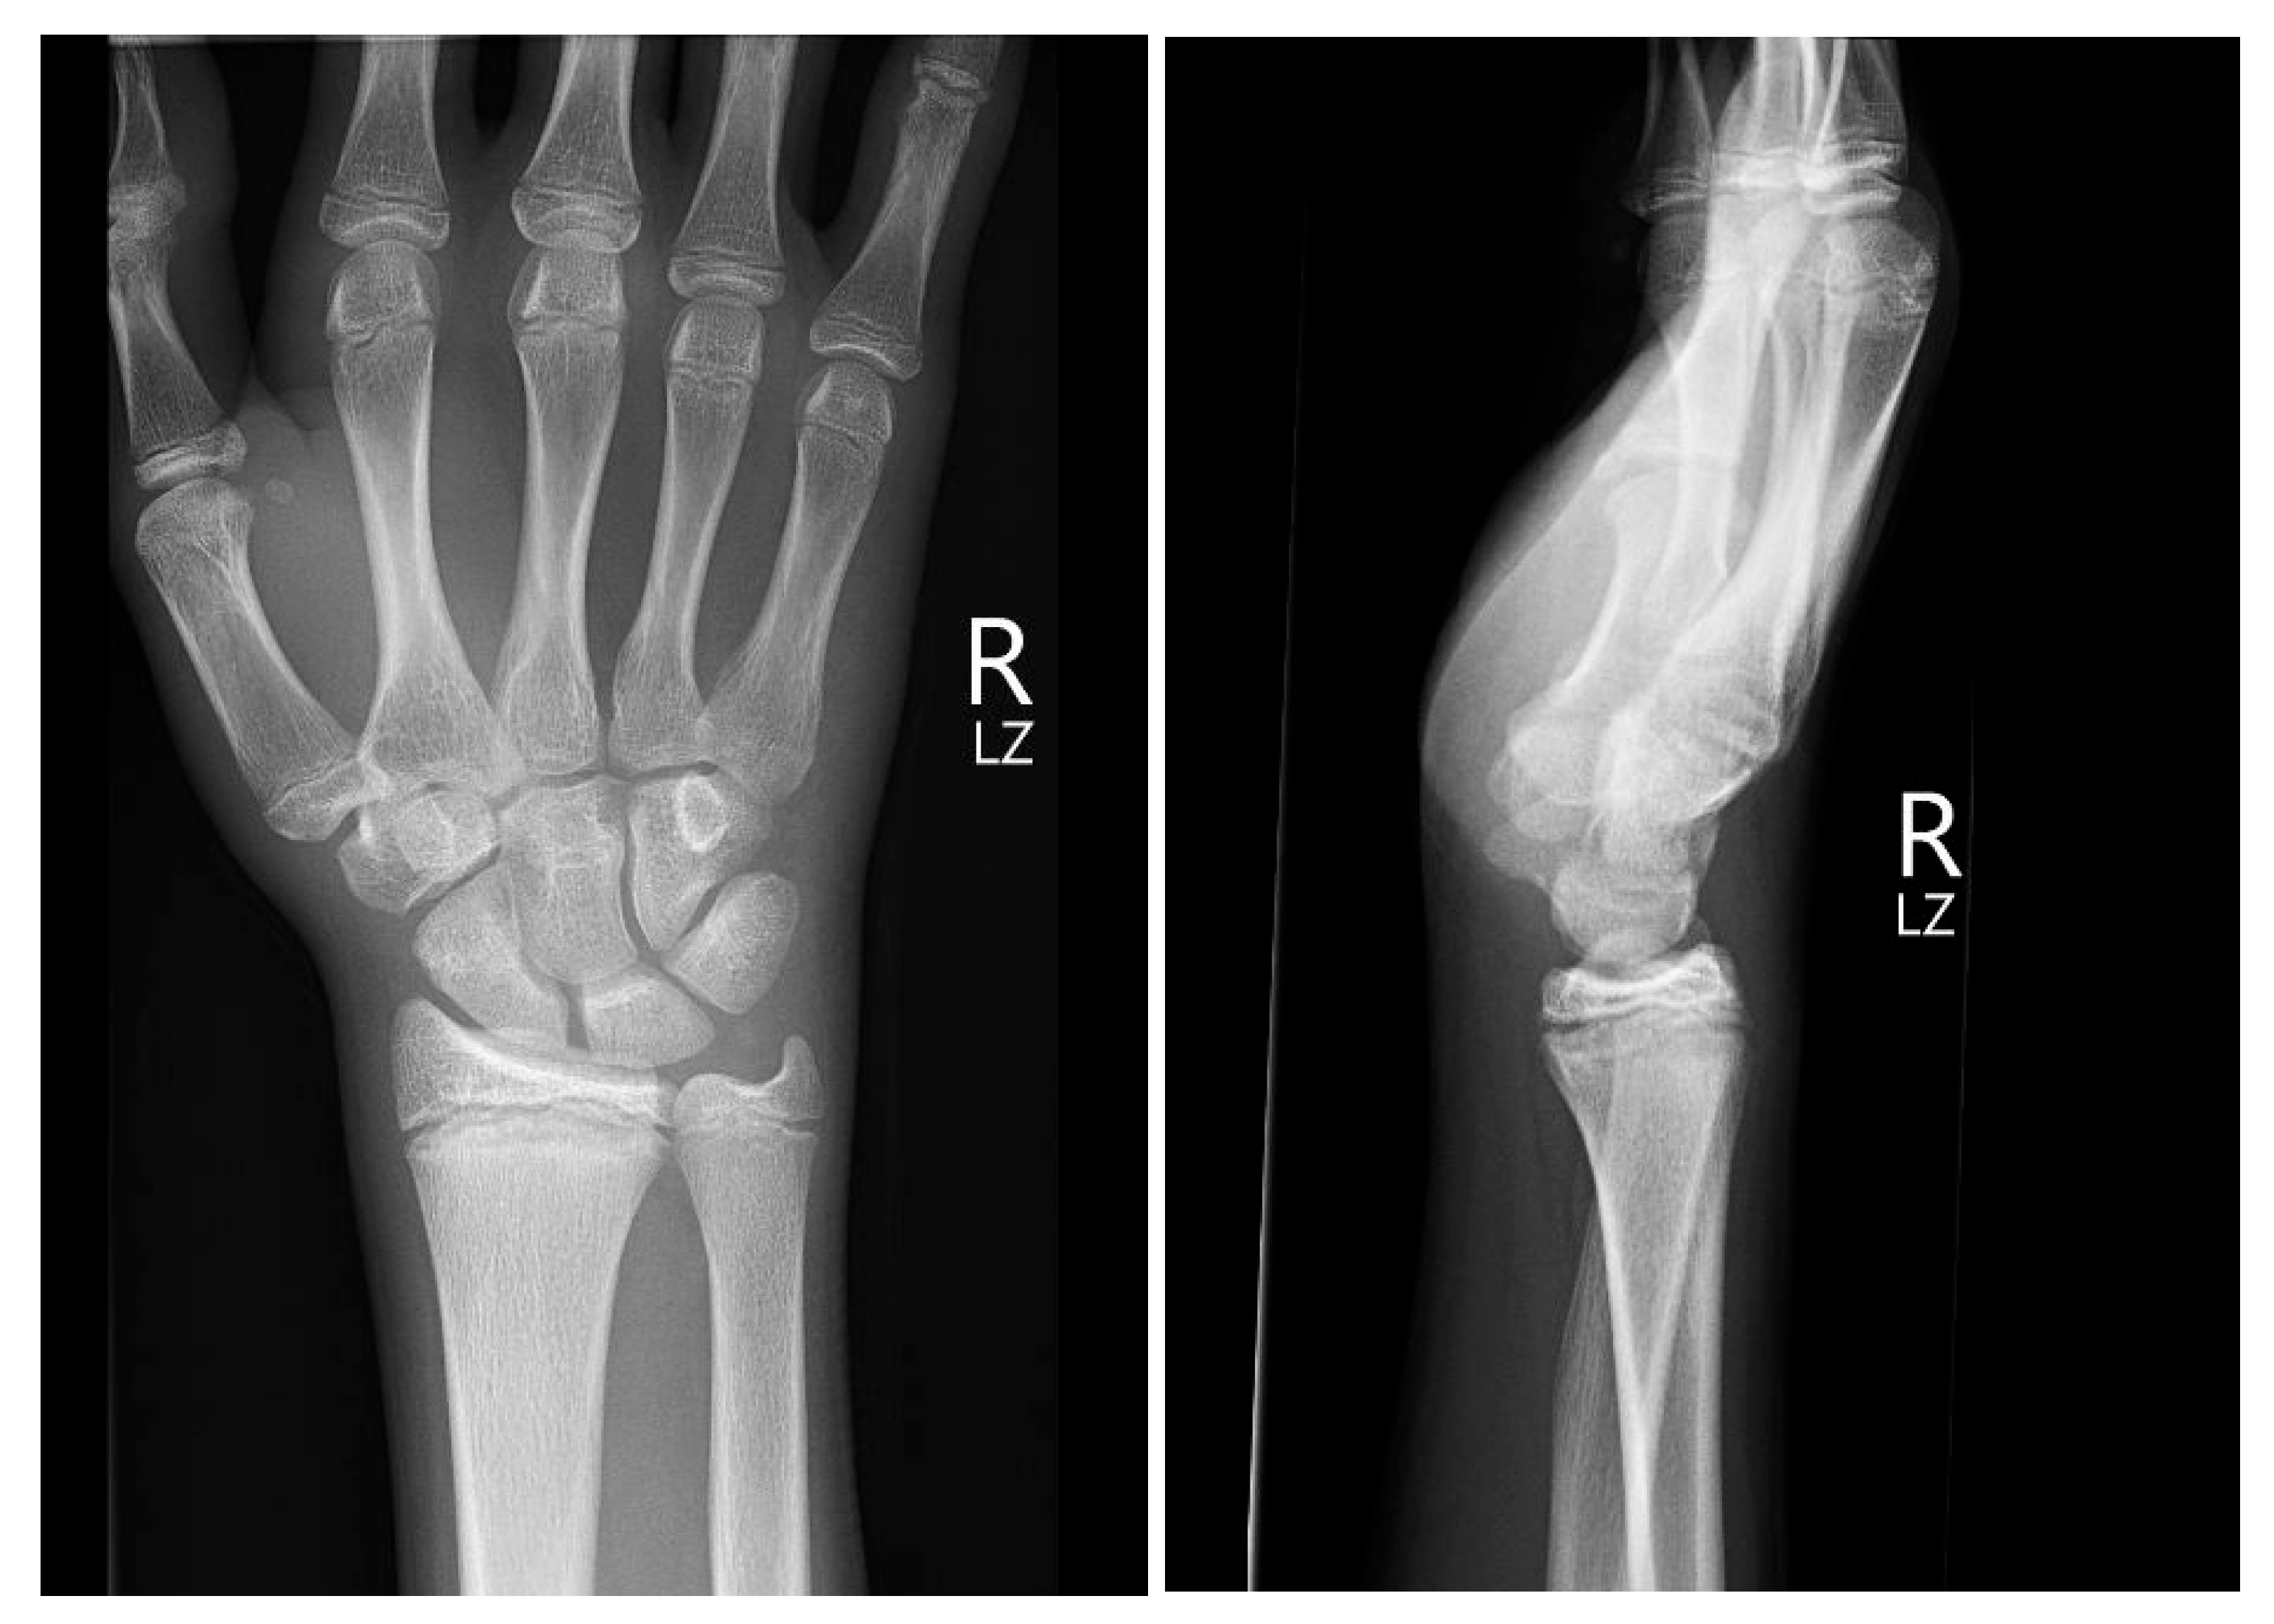

Initial conventional radiographic assessment showed no definitive fracture, with a potential suspicion of a proximal radius fracture (Figure 1). Due to significant tenderness over the radial fossa and pisiform, a CT scan was performed, confirming a nondisplaced scaphoid fracture and a suspected pisiform fracture with dislocation (Figure 2).

Figure 1.

Initial X-ray views in ap (left) and lateral (right) planes.